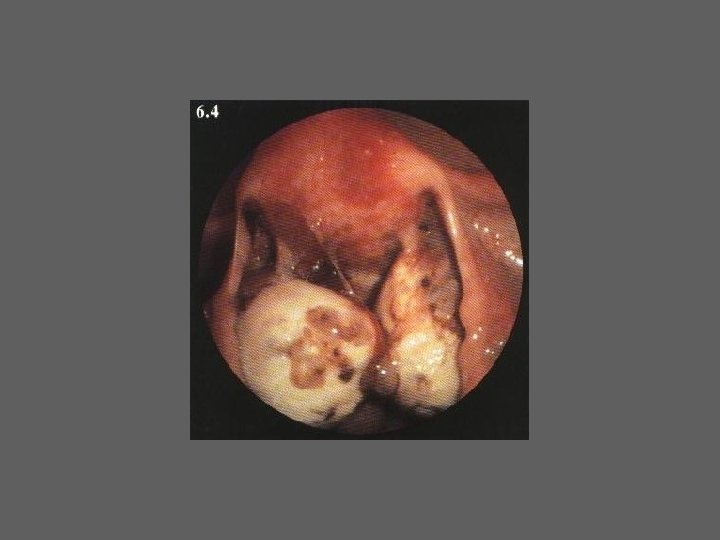

HISTEROSCOPIA - INDICAÇÕES Todas a situações em que se julgue vantajosa uma visualização completa da cavidade uterina, em particular: – Metrorragias – Dismenorreia adquirida – Infertilidade – Abortamentos de repetição e parto pré-termo – HSG anormal – DIU “perdido” – GIFT e ZIFT – Tratamento cirúrgico da patologia intracavitária: ● pólipos, miomas, septos, sinéquias, recessões endometriais ● baixos custos, reduzida morbilidade

HISTEROSCOPIA - MATERIAL CO 2 – Insuflador – Metrorragias max. 100 ml /min p < 100 mm Hg liquido (soro glicosado, dextrano, etc. ) – Fonte de luz fria – Histeroscópio (3, 5, 7 mm) – rígido ou flexível – Bainha e instrumentos cirúrgicos (pinça de biopsia, tesoura, etc.